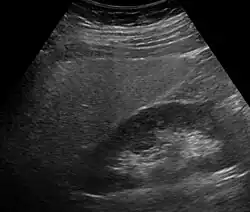

Fettleber in der Sonographie: Die Leber (links im Bild) ist deutlich echoreicher (heller) als die angrenzende rechte Niere.

Eine Leberverfettung fällt meistens in einer Sonographie durch Vergrößerung und erhöhte Echogenität im Vergleich mit der Niere[12] sowie durch eine plumpe Form oder in einer Computertomographie oder Magnetresonanztomographie auf. Wenn aus anderen Gründen eine Biopsie der Leber durchgeführt wird, lässt sich die Fettleber auch histologisch sichern. Laborchemisch lässt sich kein sicherer Nachweis führen, allerdings fallen oft leicht erhöhte Transaminasen und eine erhöhte γ-GT auf.[13] Es gibt auch die Möglichkeit, mit Hilfe von Körpergröße, Körpergewicht, γ-GT, Triglyceriden und Bauchumfang den Fettleber-Index zu berechnen, der die Wahrscheinlichkeit für das Vorliegen einer Fettleber vorhersagen kann.[14] Der Schweregrad kann mittels spezieller Kernspintomographie- oder Elastographie-Methoden bestimmt werden.[15]